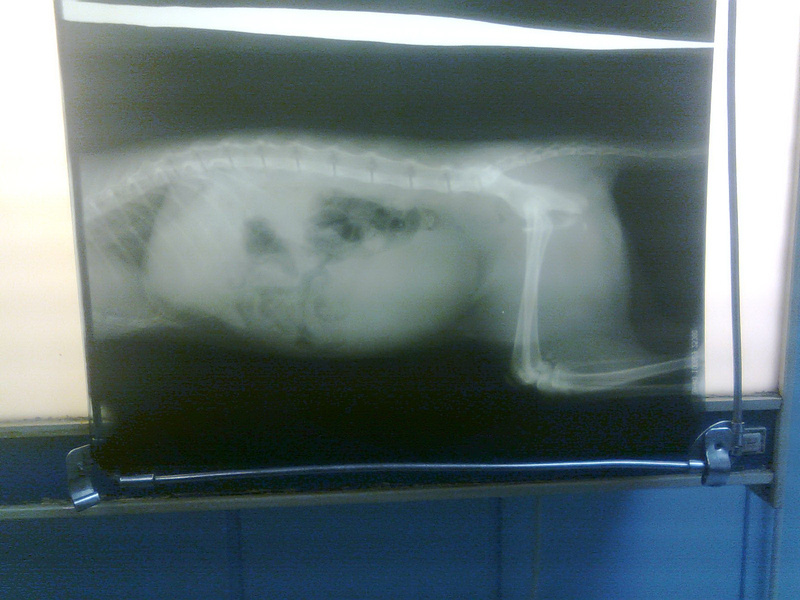

Диагноз:

Перелом костей таза с частичным нарушением целости позвоночника (более полный диагноз - см. фото ниже - не смог все разобрать, т.к. почерк не везде можно понять), атония мочевого пузыря.

Что делать: Требуется срочная операция (назначена на завтра на 15:00).